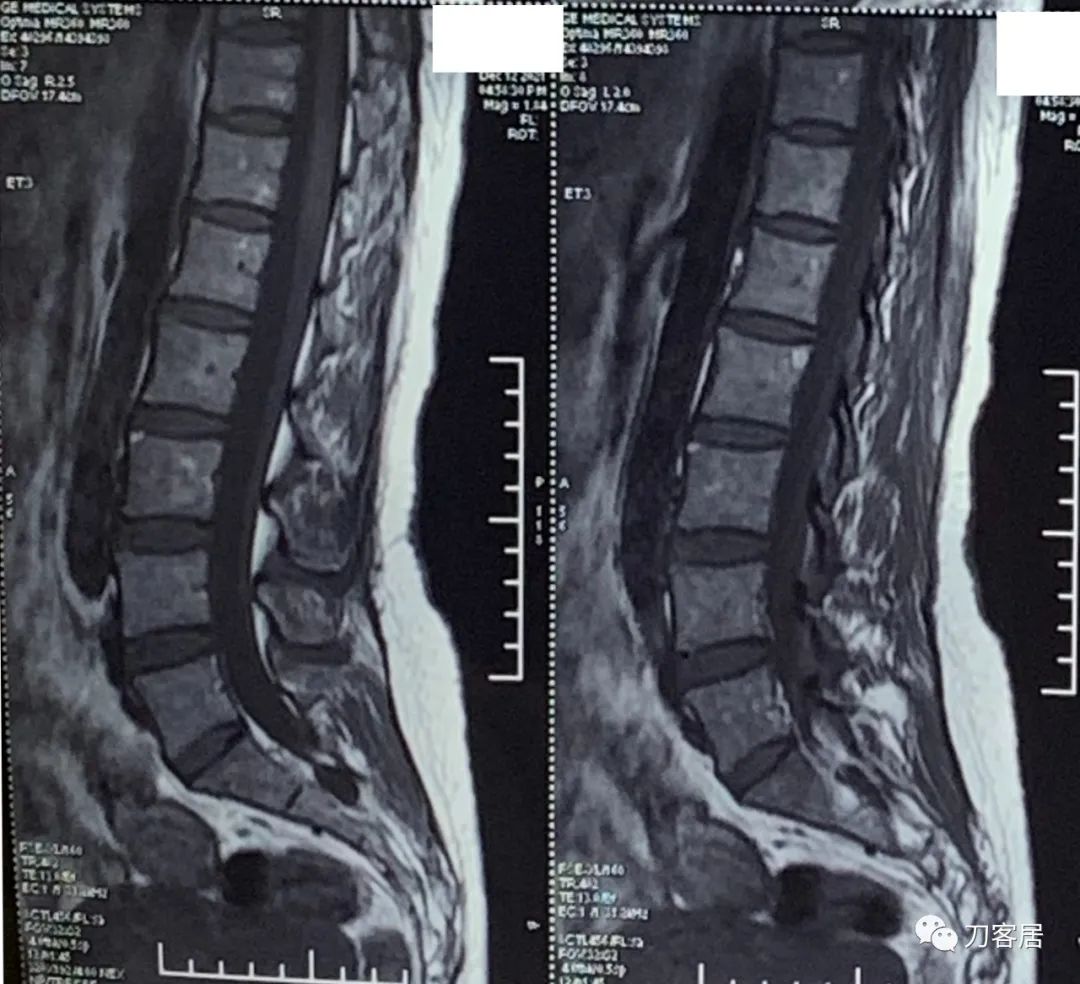

自带腰椎MRI检查未见异常。腰椎X线片提示左侧腰5横突肥大。自带外院骨密度检查结果正常。

20211212西京医院腰椎MRI.